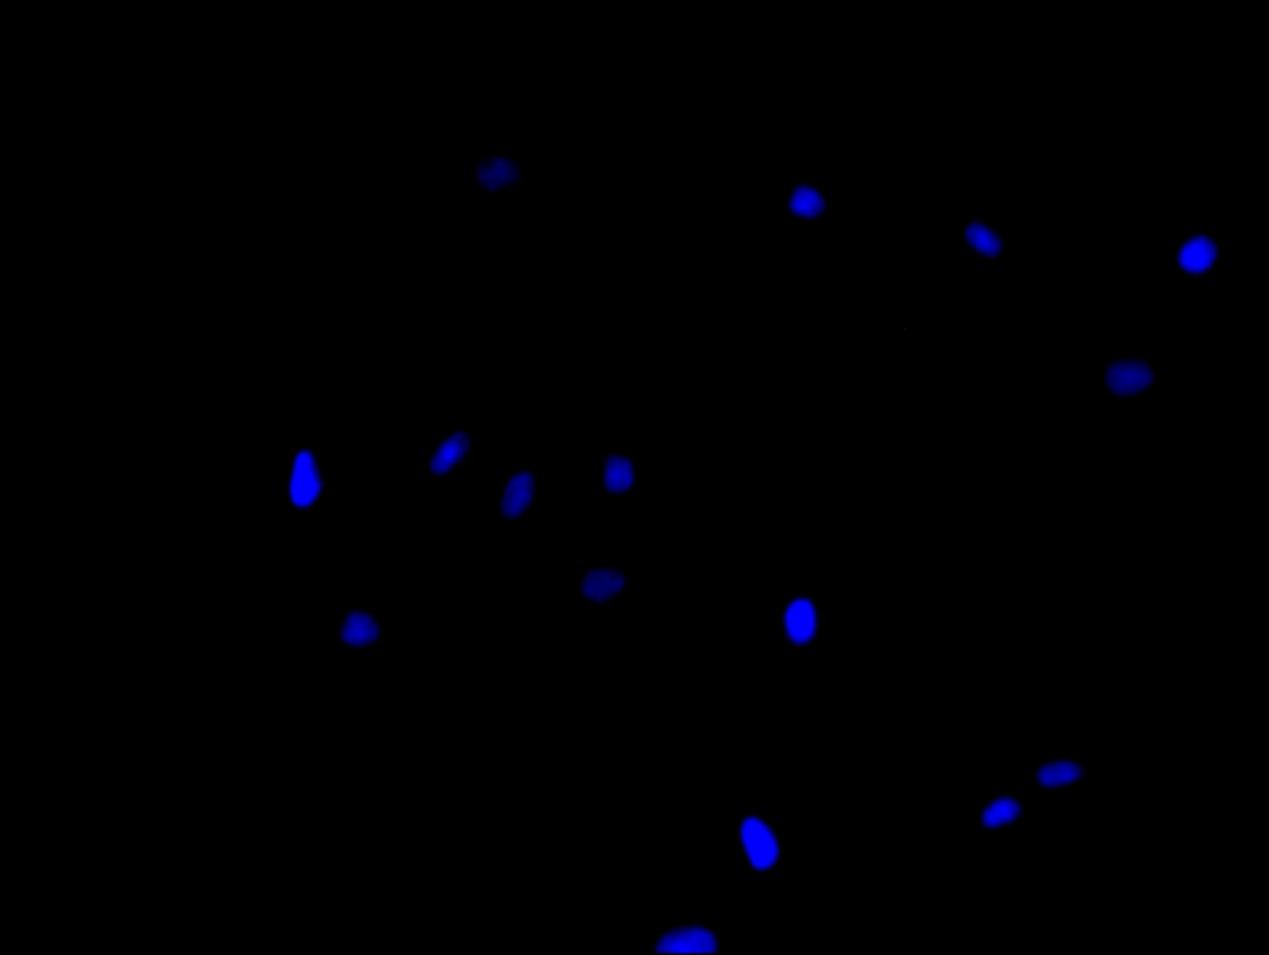

Immunofluorescence staining of A549 cell with 5% goat serum, counter-stained with DAPI. The cells were fixed in 4% formaldehyde and blocked in 10% normal Goat Serum. The cells were then incubated with the antibody overnight at 4C. The secondary antibody was Alexa Fluor 488-congugated AffiniPure Goat Anti-Rabbit IgG(H+L).

Immunofluorescence staining of SY5Y cell with 5% goat serum, counter-stained with DAPI. The cells were fixed in 4% formaldehyde and blocked in 10% normal Goat Serum. The cells were then incubated with the antibody overnight at 4C. The secondary antibody was Alexa Fluor 488-congugated AffiniPure Goat Anti-Rabbit IgG(H+L).